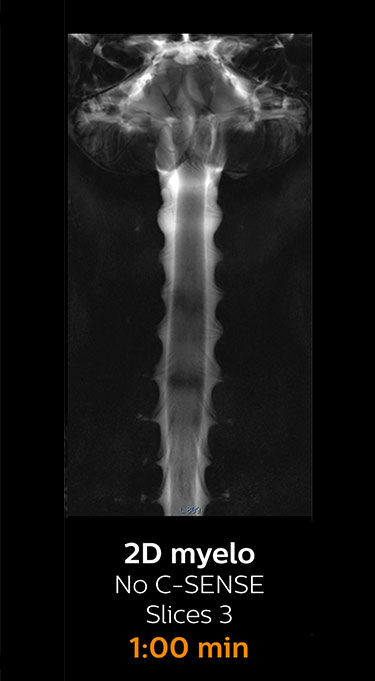

With Compressed SENSE, the scan time for the routine lumbar spine examination at KNC was reduced from 11:41 to 8:17 minutes,

MRI examination of the lumbar spine with Compressed SENSE

Ingenia 3.0T CX

Scan time 8:17 min. (was 11:41 min. without Compressed SENSE)